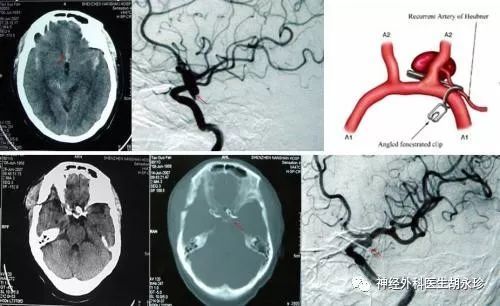

颅内动脉瘤到底应该怎么治疗

动脉瘤如何治疗?不同部位的动脉瘤治疗上有所差异。主要治疗为手术治疗和动脉瘤腔内修复术及动脉瘤栓塞。

动脉瘤应该怎么治疗?(1)针对非常小的未破裂的动脉瘤,小于7毫米的动脉瘤影像学检查,全面评估他的动脉瘤

也是很重要的,目前,治疗脑动脉瘤的方法有两种,非手术治疗以及手术治疗,具体的介绍如下。一、脑动脉瘤的